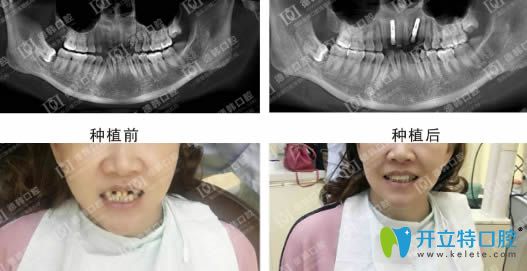

說(shuō)一千,道一萬(wàn),武漢德韓種植牙到底怎么樣,不如效果展示來(lái)的實(shí)在:

德韓口腔種植牙效果前后對(duì)比圖